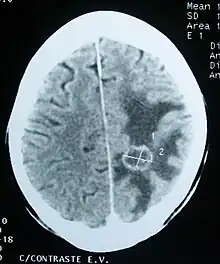

An increase in cerebral water content is called cerebral edema and it usually results from traumatic brain injury (TBI), subarachnoid hemorrhage (SAH), intracerebral hemorrhage (ICH), subdural hematoma, ischemic stroke, brain tumors, infectious disorders and intracranial surgery. Cerebral edema may result in compromised regional cerebral blood flow (CBF) and intracranial pressure (ICP) gradients which could lead to death of the affected.[1] Increased ICP leads to increased intracranial volume. Unmonitored ICP leads to brain damage by global hypoxic ischemic injury due to reduction in cerebral perfusion pressure (CPP) which is found by subtracting the ICP from mean arterial pressure (MAP), cerebral blood flow, and mechanical compression of brain tissue due to compartmentalized ICP gradients.[2] Cerebral edema is mainly classified into cytotoxic edema, vasogenic edema and interstitial edema. Cytotoxic edema affects both the white and gray matter and results from the swelling of cellular elements such as neurons, glia and endothelial cells. Vasogenic edema affects white matter and results from blood brain barrier (BBB) breakdown. Interstitial edema results from lack of proper cerebrospinal fluid (CSF) absorption.[1]